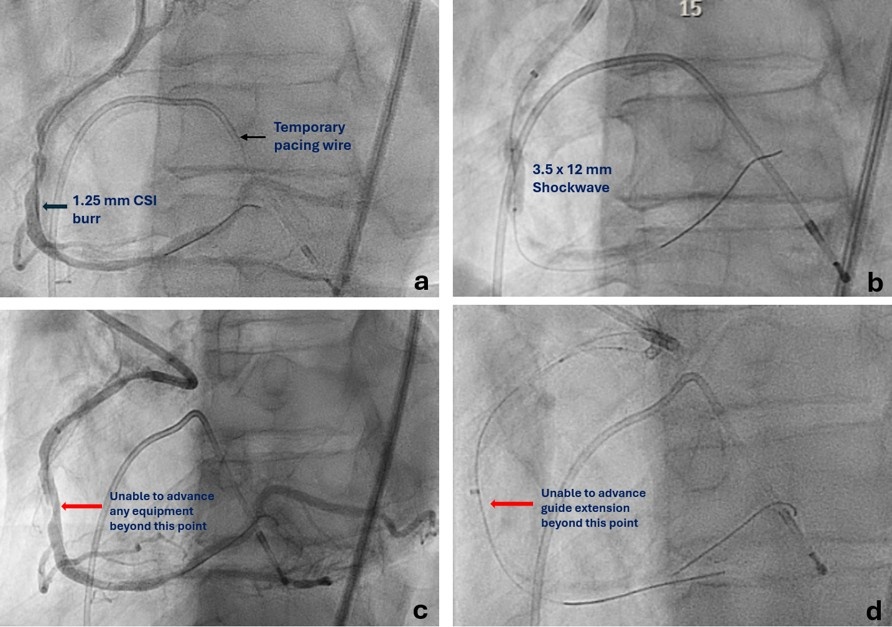

A 65-year-old man presented with unstable angina and calcified right coronary artery (RCA) stenosis (Figure 1) on diagnostic catheterization via radial approach. Percutaneous coronary intervention (PCI) was performed via 7F femoral access using a Judkin’s Right (JR) 4 catheter followed by an Amplatz Left 0.75 guide catheter. Orbital atherectomy (aborted after 6 runs at low-speed because of no-reflow) followed by intravascular lithotripsy (IVL) using a 3.5 mm Shockwave C2+ (Shockwave Medical) was performed. Following this, no equipment could be advanced beyond the mid-RCA calcified nodule (Figure 2).